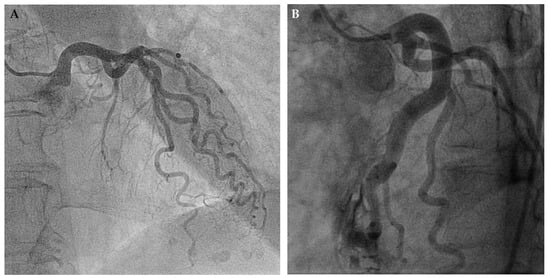

- Zbinden, R.; Zbinden, S.; Windecker, S.; Meier, B.; Seiler, C. Direct demonstration of coronary collateral growth by physical endurance exercise in a healthy marathon runner. Heart 2004, 90, 1350–1351. [Google Scholar] [CrossRef] [PubMed][Green Version]